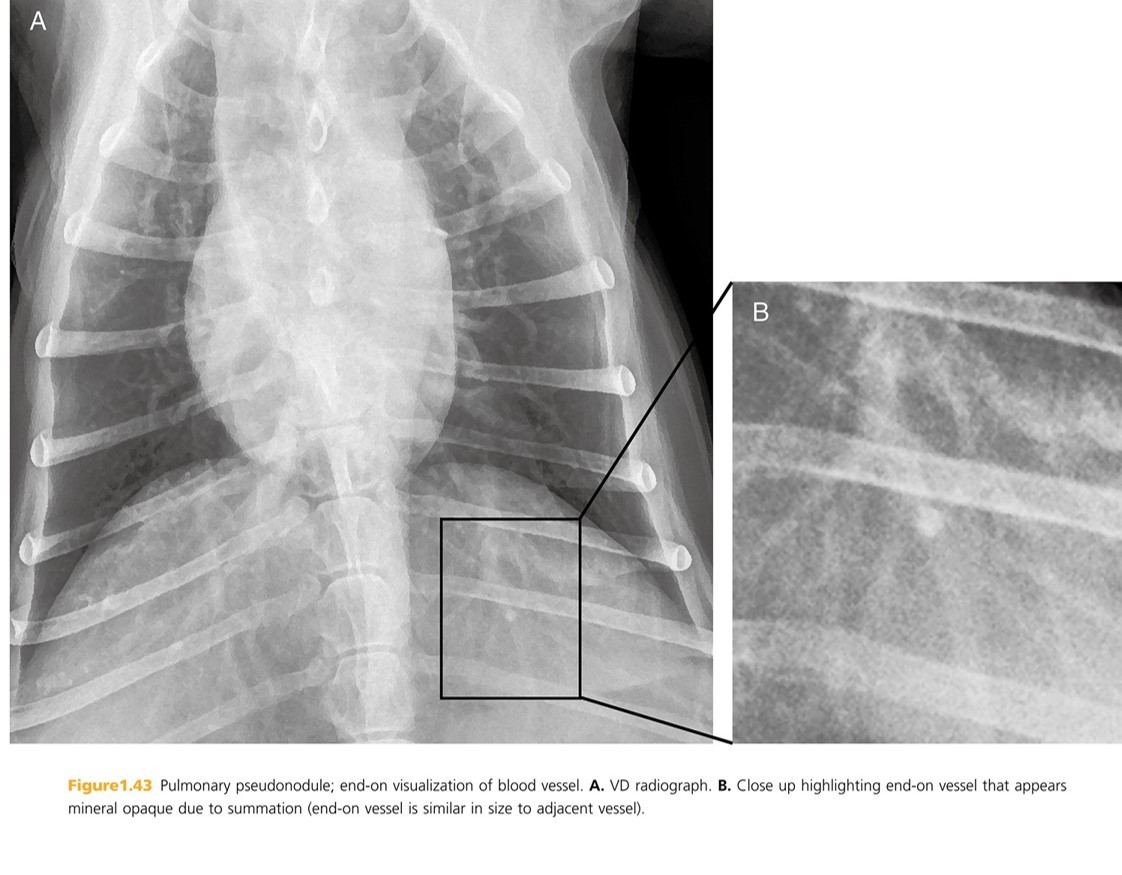

Pseudo-nodules are discrete soft tissue or ______ opacity that mimic pulmonary nodules.

mineral

Neoplastic pulmonary nodules ______ mineralize. If a nodule is more opaque than nearby vessels of same size, it represents _____ minrealization or end-on visulization of a _____.

rarely

focal

vessel